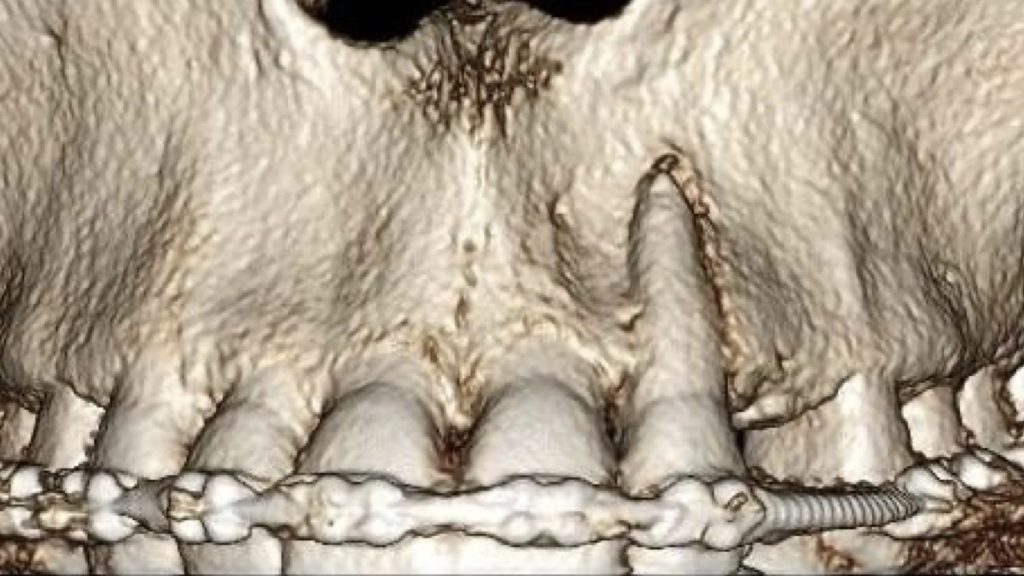

A 24-year-old female patient referred by an orthodontist who resolved the unilateral agenesis of the left upper lateral incisor by mesializing the left upper cuspid and shifting the gap in between teeth 23 and 25. After confirming the free bone corridor between the roots of the cuspid and the first bicuspid, a Straumann BLX RB implant (3.75 mm) was inserted and thin soft tissue buccally augmented with tuberosity connective graft. A sliding island flap on the palatal side relieved tension while suturing both sides of the mucosa. Three months later, the ortho appliance was removed and a temporary crown (Cerasmart) was delivered. All teeth were whitened and after four-month-period, an all-ceramic crown (Katana) was made and fixed. The patient denied and reshaping of the tooth 23. In 3 years, the situation is sthbilized however the prognosis of the tissue covering the tooth 23 is doubtful. Prosthetic part of the treatment done by a.krugova

sufficient bone width in cuspid area